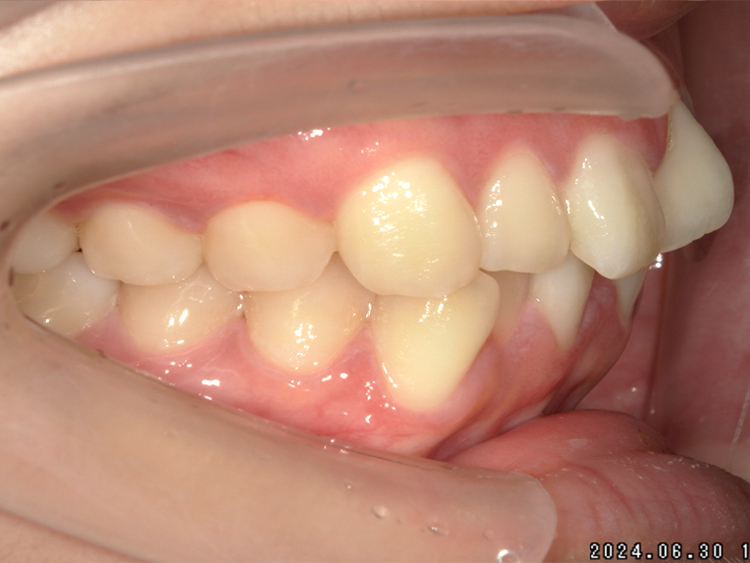

症例5

Before

After

| 主訴 | 上下3-3の並びが気になる |

|---|---|

| 年齢 | --- |

| 治療 期間 |

約1年 |

| 治療 内容 |

インビザライン5-5 |

| 治療費 | ¥517,000(税込)/調整料含む |

| 治療のリスク | 奥歯を動かさないので、前に出して並べていく。 歯と歯が移動するスペースを作るので、知覚過敏の症状がまれにでる。 歯を動かすことで、歯茎が下がるリスクある。 矯正終了後は、リテーナーを使用し、後戻りを防ぐ必要がある。 |